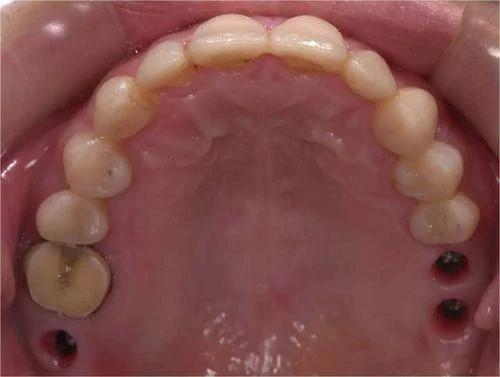

2、一些脱敏牙膏使用较方便,适合症状较轻者用。如果病因是龋坏,则需去除病变组织,用材料“补牙”。如果牙本质暴露的面积太大或药物涂擦法效果不佳则应作牙冠覆盖牙齿,以保护牙齿。坚持早晚刷牙,坚持温水刷牙,坚持吃水果或者任何东西后刷牙。可以减轻或者控制牙齿发酸。

4、补牙后牙齿酸软是一个正常的术后反应,特别是龋坏较深的情况下,一般观察一段时间后酸软症状会消失,根据个体差异一般需观察2周到2月时间不等。你好,这种情况是在做根管治疗,积极配合医生治疗。避免咬食硬物。 建议多喝水,饮食以清淡好消化为主,禁食辛辣食品,补牙后近期避免咬食硬物。多观察。如果酸软症状仍不消失甚至出现疼痛不适此时可能需要行根管治疗术。

5、补牙材料能保持多久?补牙后牙齿的使用时间与补牙的材料选择有着密切的联系。牙洞如果较大、较深且形状不规则,或是邻面牙洞,则充填好的牙齿就应小心使用。否则,咬硬物时易出现牙齿劈裂或充填物脱落。补牙后牙齿的使用时间与日常的口腔保护有关,如平时多注意口腔的清洁,以及养成良好的用牙习惯,那么补牙后的牙齿可以是终身的。